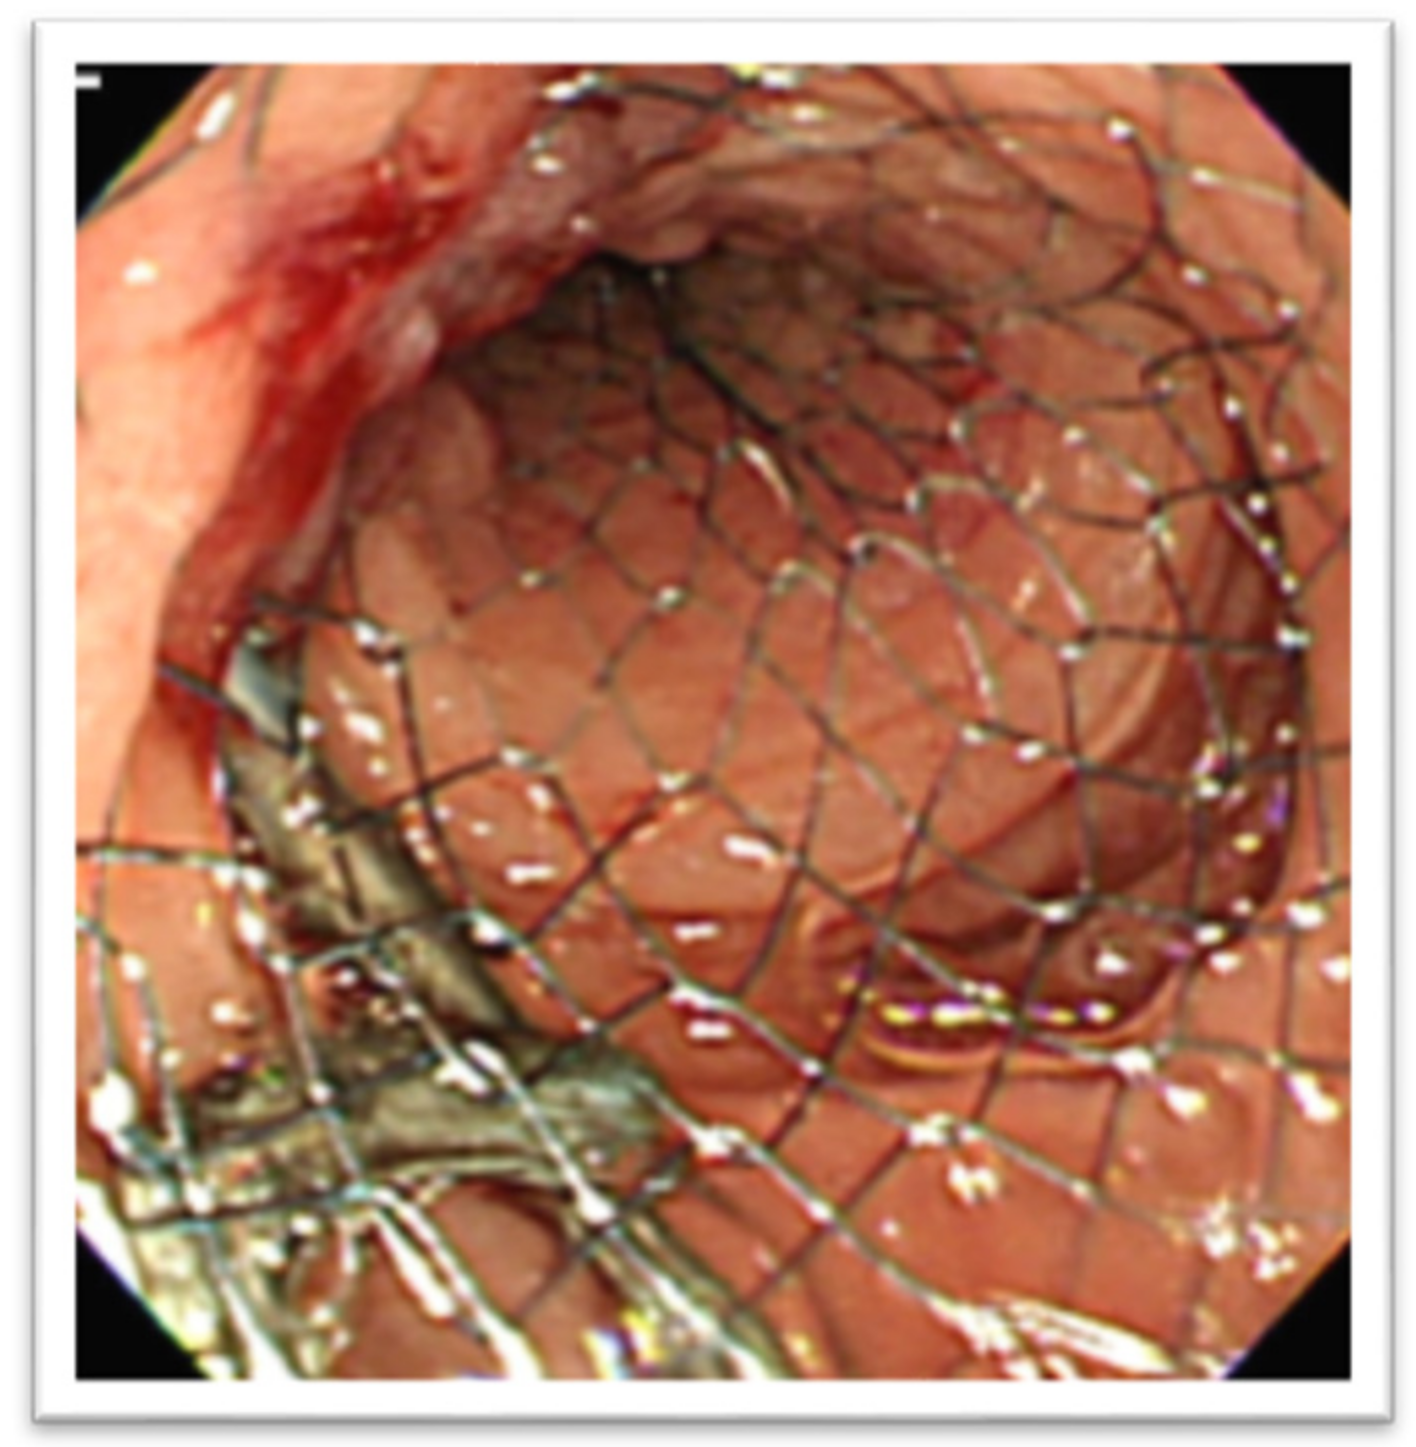

In the setting of malignant GOO, several randomized trials have compared the outcomes of surgical gastrojejunostomy (SGJ), endoscopic SEMS placement (Figure 11), and EUS-GEA anastomosis (Figure 12) [2,13,14,15,16,17]. The main limitation of SGJ is commonly considered its invasiveness, associated with the occurrence of post-surgical adverse events, as with gastroparesis and post-operative infections [2,13].

Figure 12. Lumen-apposing metal stent in the context of EUS-GEA.